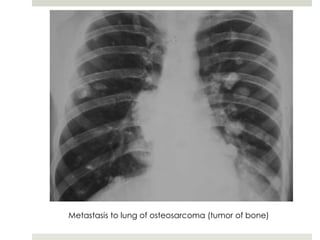

Metastasis to lung of osteosarcoma (tumor of bone)